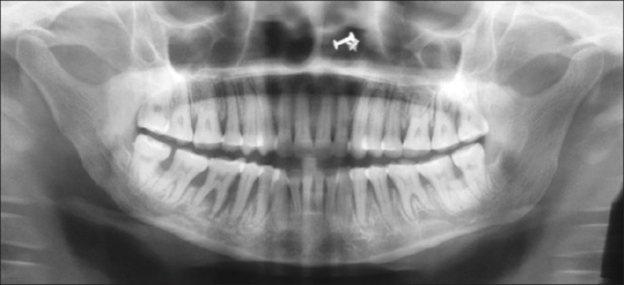

Radiographs may show varying degrees of bone resorption in patients with scleroderma. Mandibular resorption has been reported in 10% to 33% of patients with systemic sclerosis.11 Osteolysis is documented resorption of the mandibular angle and condyle of adult patients with scleroderma (see Figure 3). The etiology is not known. However, it is theorized that:

- Tightening of facial skin may exert excessive pressure on the mandible and induce bone loss

- Vasculopathy associated with systemic scleroderma may diminish the blood supply to the mandible and induce bone loss

- Atrophy of the muscles of mastication may lead to cone necrosis.

Uniform widening of the periodontal ligament space, especially around posterior teeth, is common.4,11